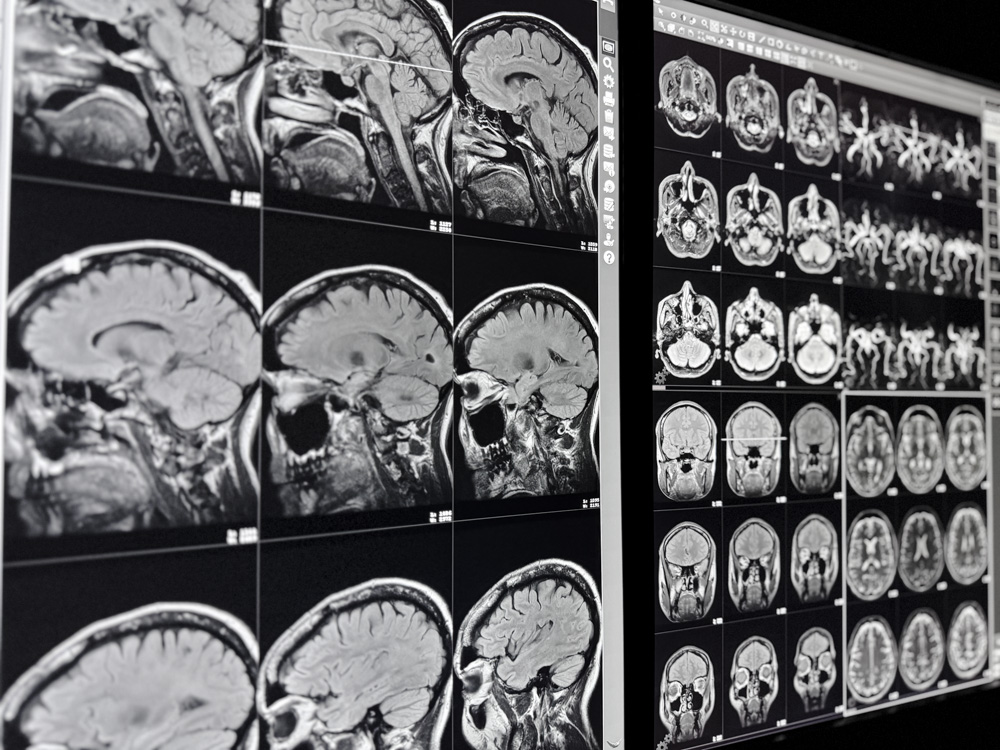

Die Magnetresonanztomograhie (MRT) ist ein bildgebendes Verfahren, das Gewebe exakt abbildet – vollkommen strahlungsfrei.

Mit diesem Verfahren, auch Kernspintomographie genannt, sind wir in der Lage, aussagekräftige Schnittbilder sämtlicher Körperregionen zu erstellen. Dabei wird die MRT als hochaussagekräftiges diagnostisches Verfahren heute routinemäßig bei verschiedensten Fragestellungen eingesetzt.

Dank des enormen technischen Fortschritts der MRT-Forschung, insbesondere der MR-Gradiententechnik und der Herstellung von organspezifischem Kontrastmittel, ist es uns heute möglich, den gesamten menschlichen Körper darzustellen – und dies nicht-invasiv, also ohne Eindringen in den Körper.